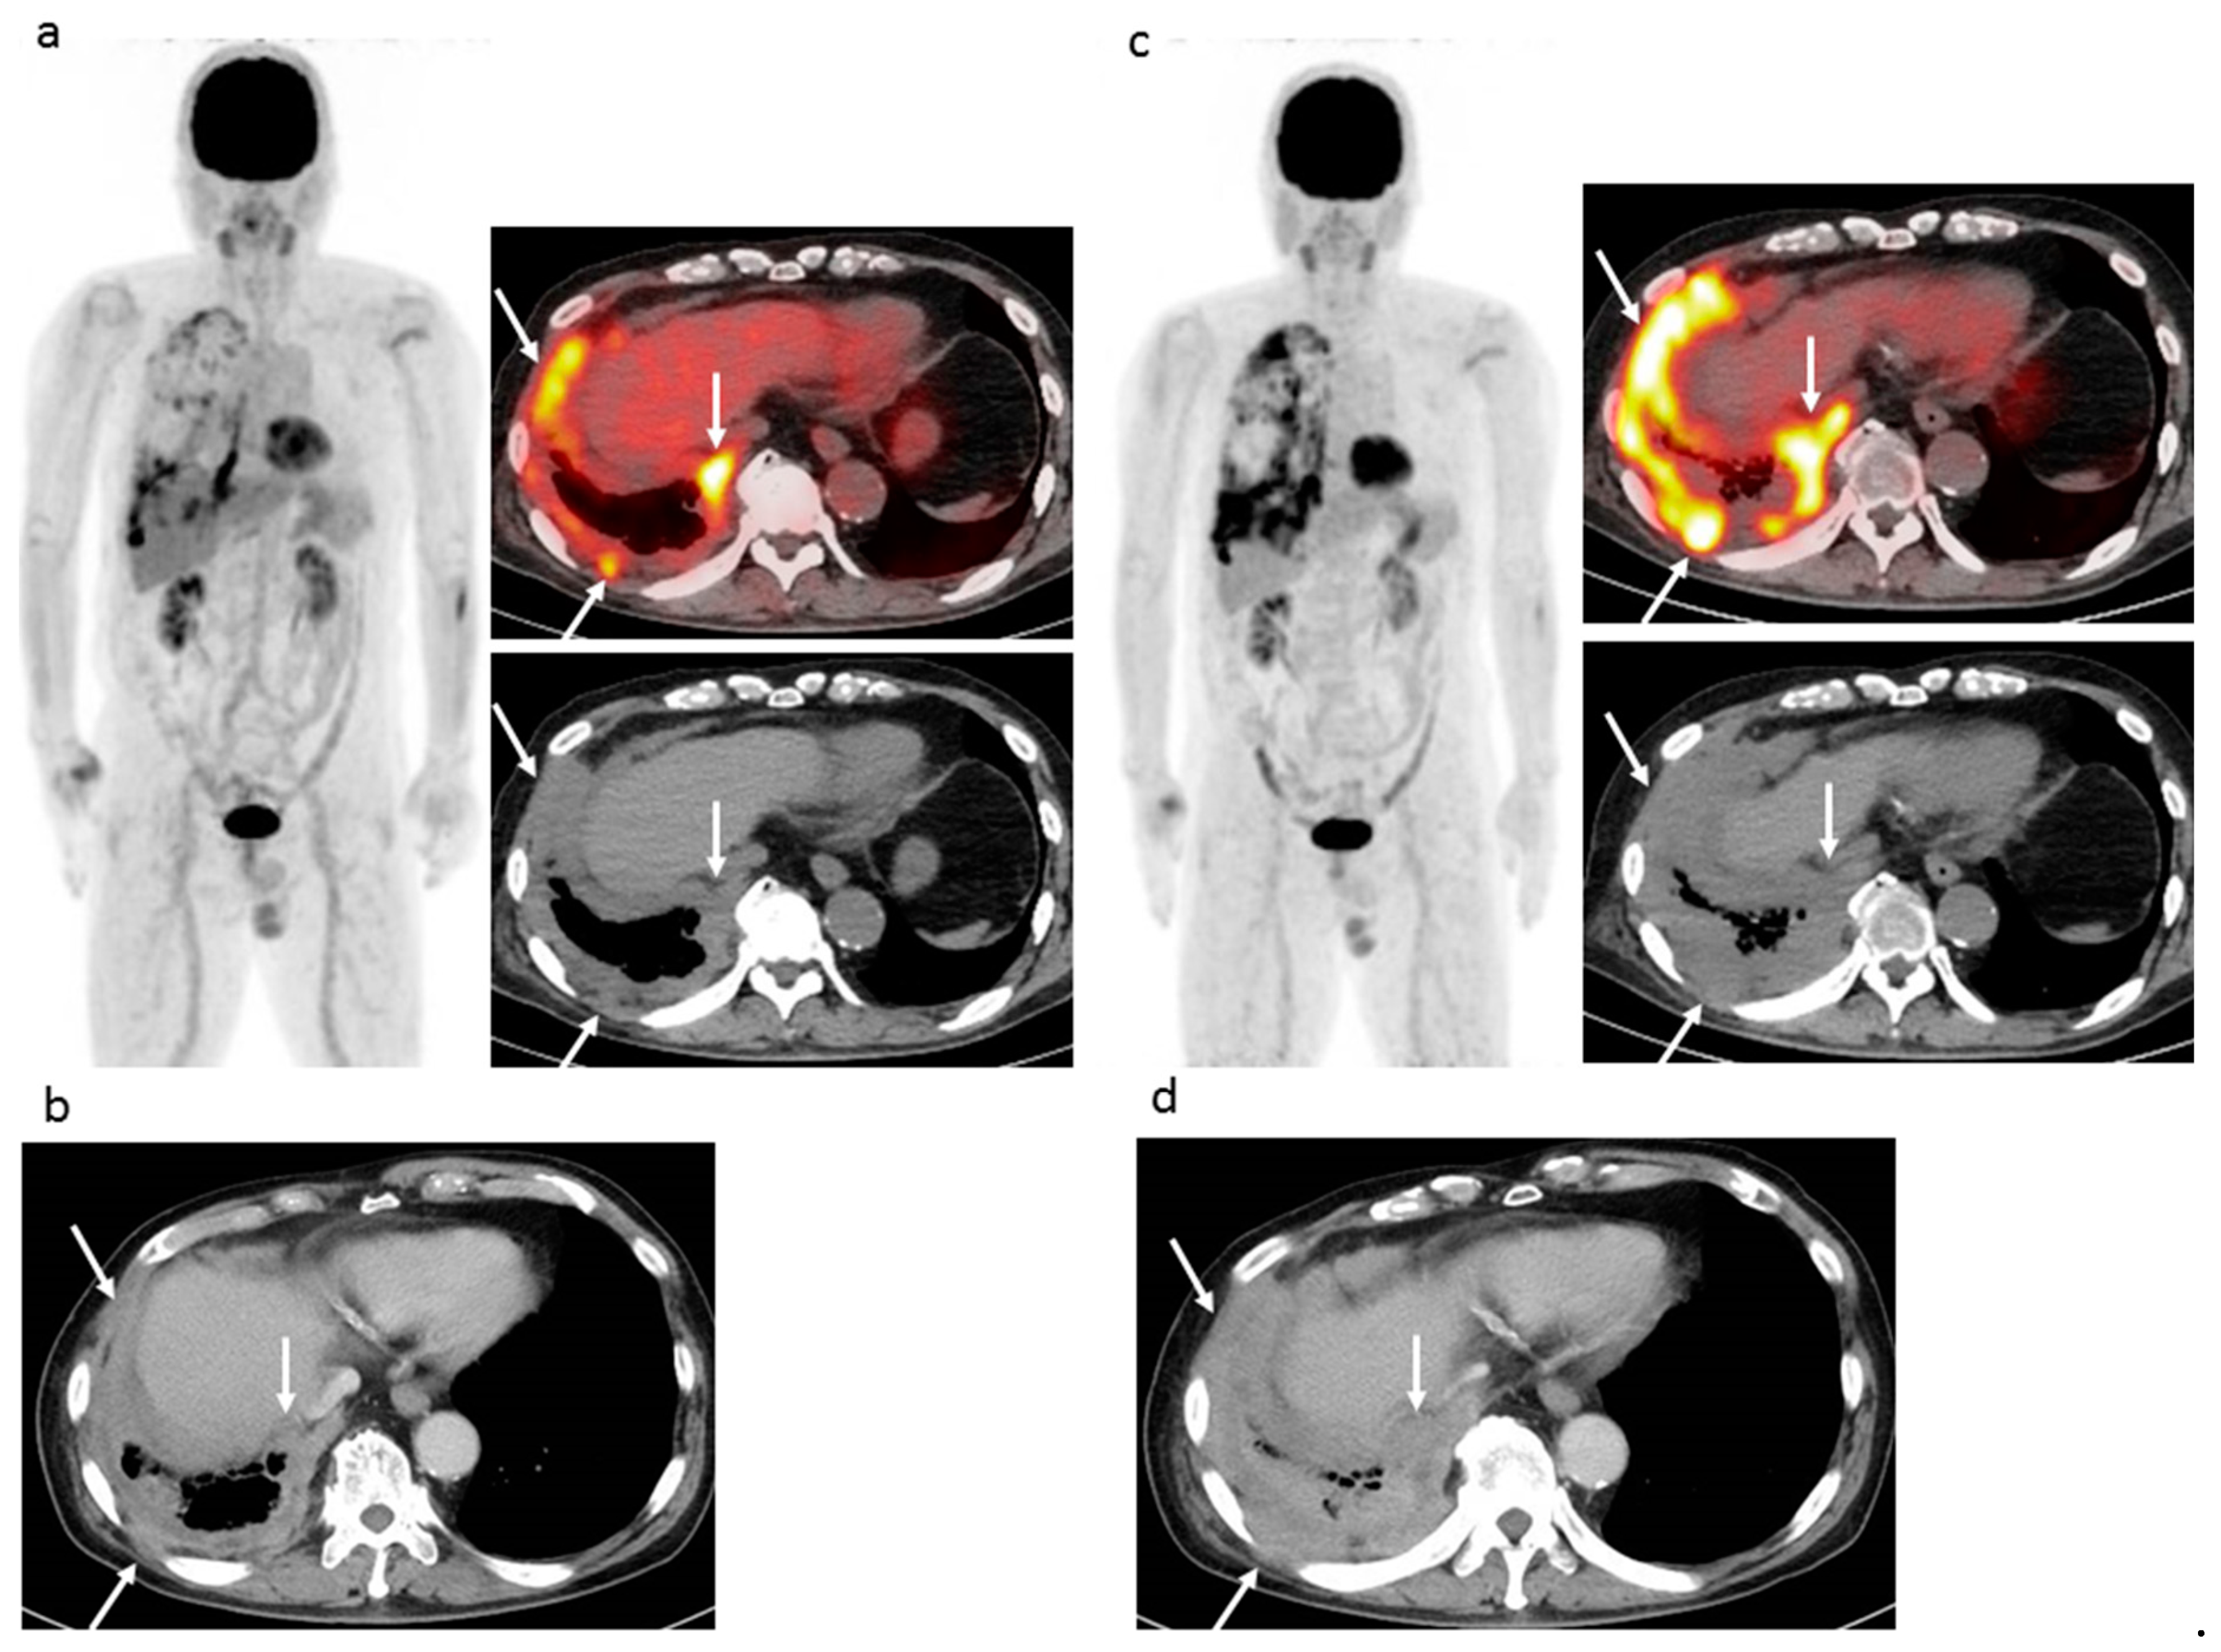

Figure 2.

74 year-old man with right epithelioid malignant pleural mesothelioma (cT2N0M0), who previously received six cycles of first-line chemotherapy (pemetrexed + cisplatin) and then 12 cycles of nivolumab as second-line chemotherapy. (a) Pre-nivolumab treatment FDG-PET/CT shows multiple areas of strong FDG uptake in areas of right pleural lesions (arrows). (b) Pre-nivolumab treatment contrast-enhanced CT shows mass-forming thickness of right pleura (arrows). (c) Post-treatment FDG-PET/CT after 12 cycles of nivolumab shows remarkable progression of multiple pleural lesions (arrows) and appearance of new pleural lesions. (d) Post-treatment contrast-enhanced CT after 12 cycles of nivolumab shows remarkable progression of pleural lesions (arrows). EORTC, PERCIST, imPERCIST, and CT criteria (modified RECIST and RECIST 1.1) indicated PMD or PD due to remarkable progression and appearance of new lesions. In FDG-PET/CT results, the SULpeak sum of the five highest level pleural lesions was increased by 98.6%. In CT findings, the sum size of six pleural lesions perpendicular to the chest wall was increased by 40.3%. According to the second (c) FDG-PET/CT and (d) contrast-enhanced CT result, the patient started another chemotherapy series (irinotecan + gemcitabine), though was alive at 13.9 months after initiation of nivolumab.